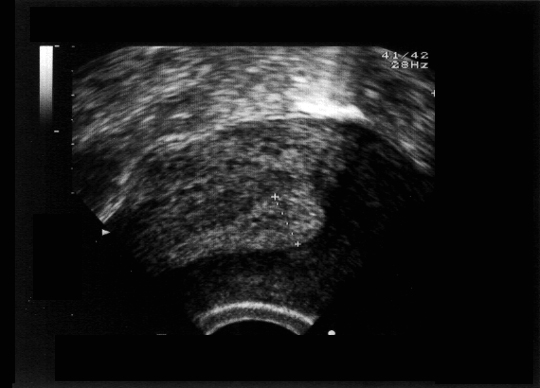

Endomètre. Au 21ème jour du cycle, l'endomètre en phase sécrétoire apparaît comme une bande échogène uniforme, avec parfois quelques images kystiques. L'épaisseur normale peut atteindre 12 mm